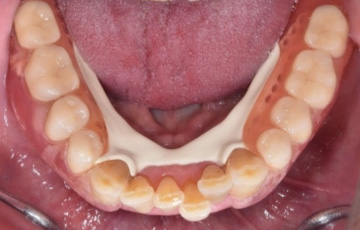

下の歯は天然歯なので歯を削らずに、「ジルコニア製ノンクラスプデンチャー」にしました。

下の歯は天然歯なので歯を削らずに金属を使わないノンクラスプデンチャーにしました。

| 金額 | 【下顎】

合計:76万円 +TAX |

| リスク | 金属と比べて衝撃に弱く破折しやすい。 |